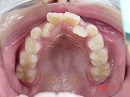

今回の場合、歯並びが悪い原因は 上顎が小さい事 でした。

拡大 矯正前 矯正後

診査・診断の結果、

上顎の大きさを約10ミリ大きくしなくてはならないことがわかりました。

今回の症例は、約6カ月ほどで改善しています。

しかし、拡大だけで将来の歯並びが良くなる訳ではありません。